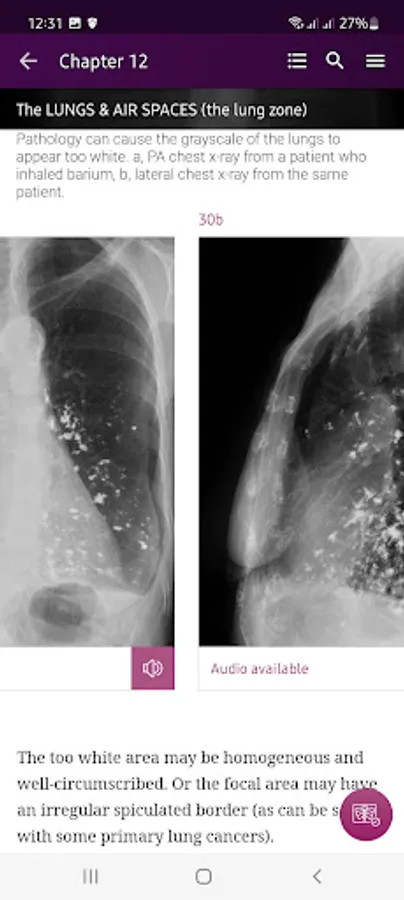

Section II* introduces the concept of radiological zones to give you a starting point in the understanding of the radiological anatomy of the chest. The next chapters review in detail the radiological anatomy of specific anatomical structures, also provide examples of how the x-ray image can change due to pathology. The final chapter explains how the individual structures come together to form the radiological image.

Pathology – Numerous interesting examples of pathology related to specific anatomical structures and regions.